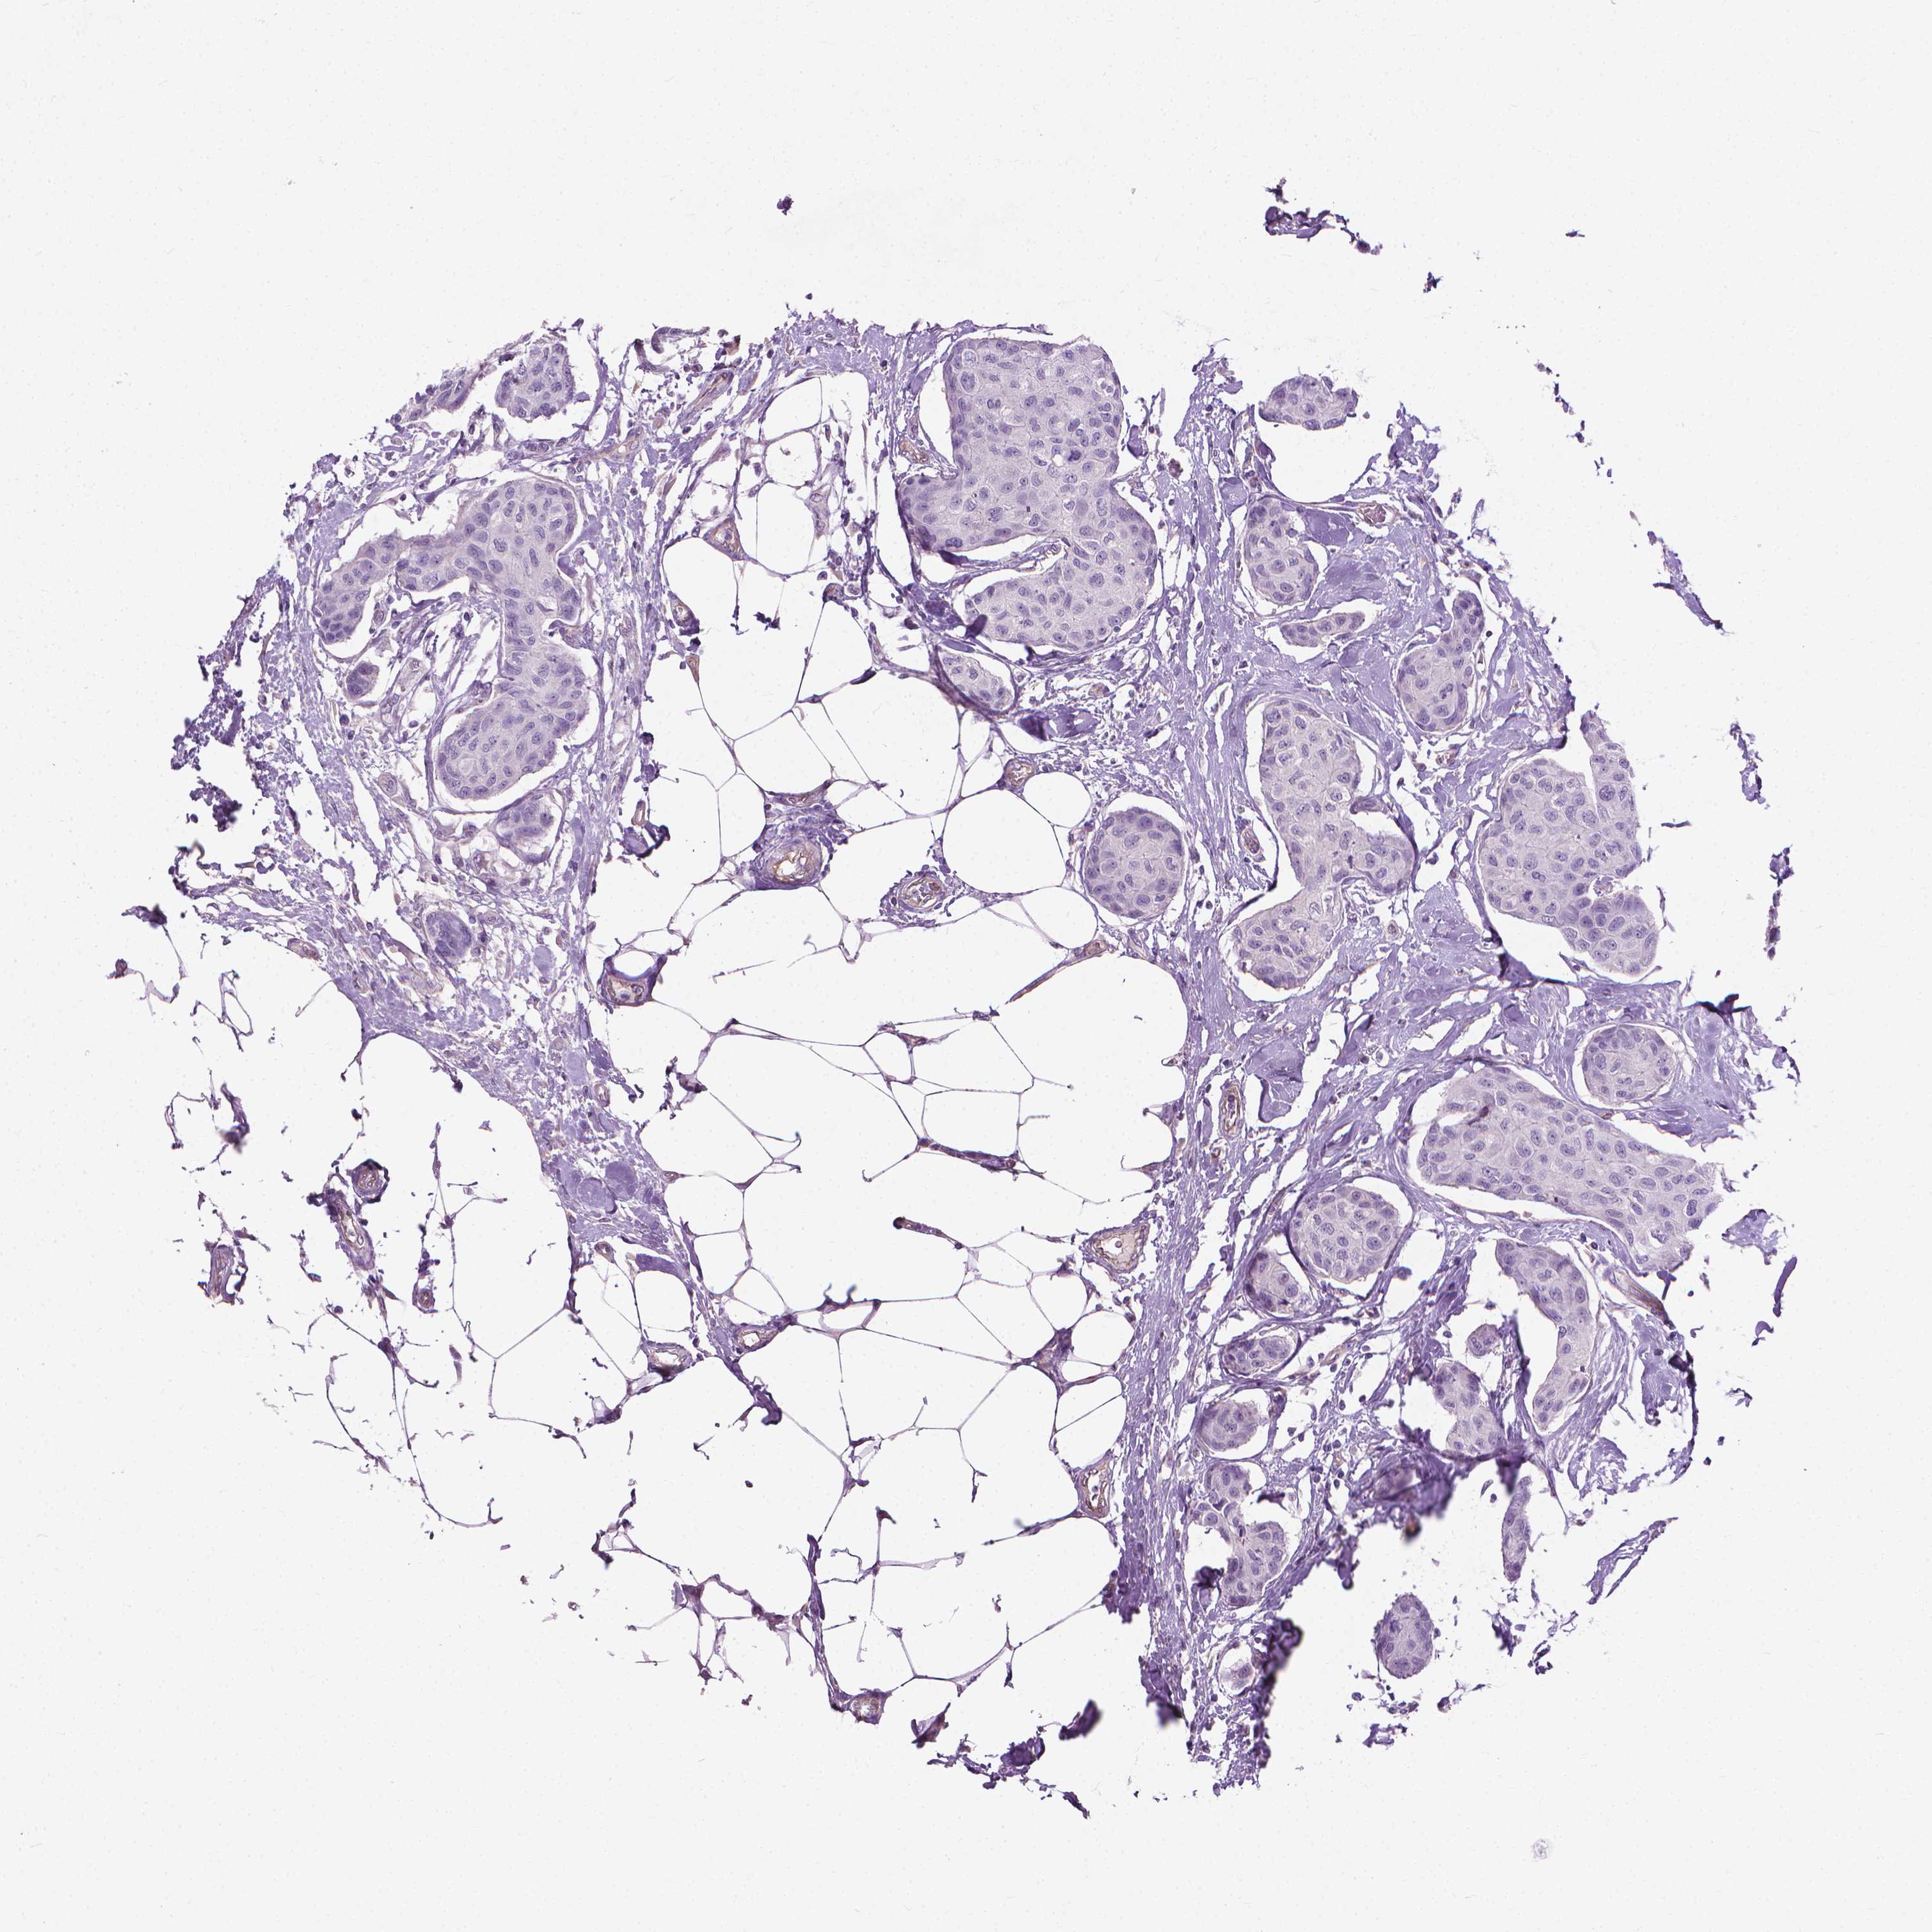

BRCA TCGA BRCA VALIDATION PROTEIN EXPRESSION